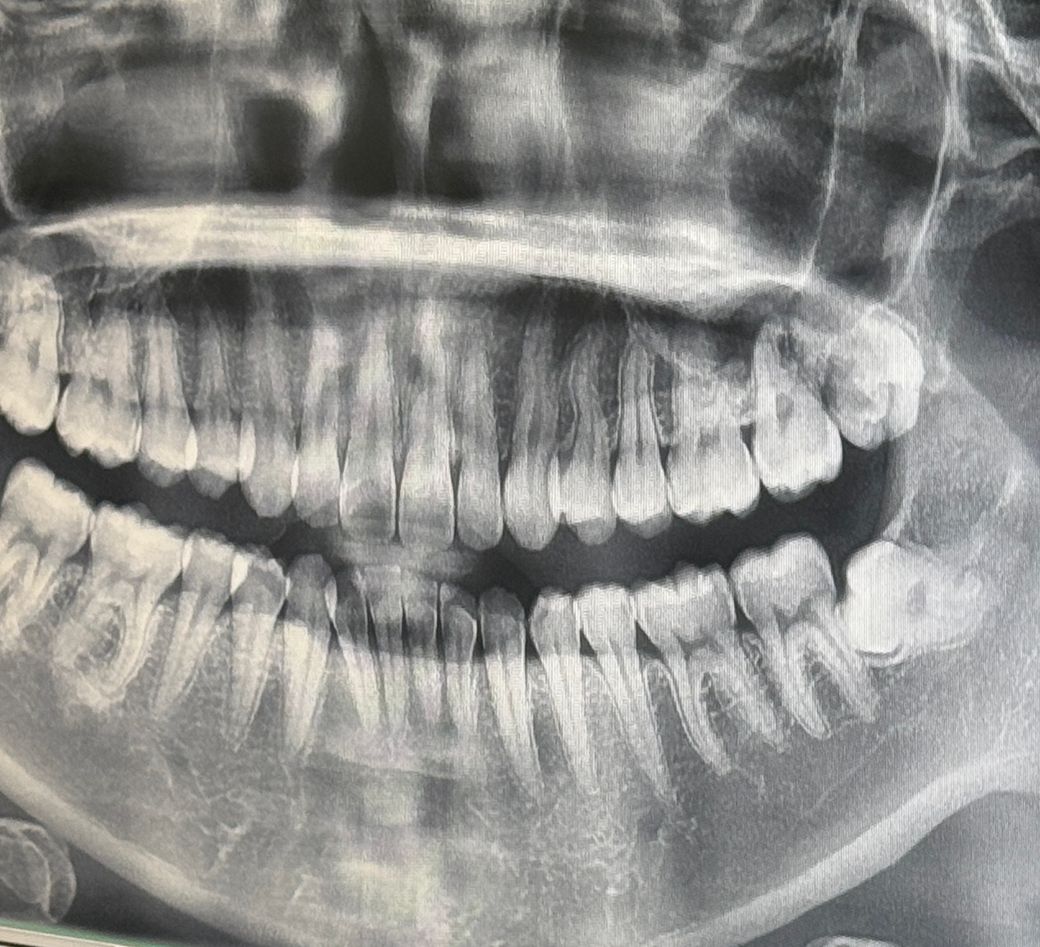

사랑니가 왼쪽 아래 위에 다 생겼습니다ㅠㅠ

혹시 신경을 지나는 경우일까요?

현재 방향이 기울어 있어 앞의 어금니를 상하게 할수 있기에 발치기 필요로 되며, 신경을 지나지는 않으나 발치시 신경이 건드려질수 있기에 숙련된 구강외과 전문의에게 발치를 받는 것이 안전합니다.

왼쪽 아래 사랑니는 신경과 아주 근접하긴 합니다 위 사랑니는 일반적으로 신경과 관계 없습니다

정확한건 CT를 찍어봐야 알겟지만 파노라마 상으로는 신경과 상당히 겹쳐 잇는것처럼 보이긴합니다.

사랑니와 신경관이 겹쳐보입니다. 사랑니의 위치를 봤을 땐 발치를 하는 게 좋아보입니다.

사진상으로는 겹쳐보이기는 하지만 ct를 찍어봐야 정확히 알 수 있는데요. 대부분은 신경관과 거리가 멀어서 발치할 수 있습니다.

아래 사랑니의 경우에는 신경관과 매우 가까워 보입니다. 사랑니가 맹출되어 있지 않고 그냥 매복되어 있다면 굳이 발치를 하지 않아도 됩니다.